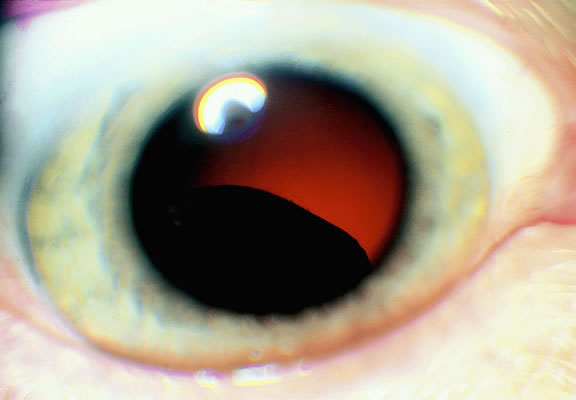

Most eyes with untreated uveal melanoma eventually develop glaucoma.74,75 Anterior tumors, that is, high-grade iris melanomas or ciliary body melanomas that invade the anterior chamber, typically cause secondary open-angle glaucoma by seeding or directly infiltrating the trabecular meshwork (Fig. 12). The latter often occurs in a circumferential or ring fashion. Posterior melanomas generally cause secondary angle closure glaucoma by stimulating iris neovascularization or by causing pupillary block. The pupil is blocked when large tumors or tumors that have caused highly elevated total retinal detachments displace the lens iris diaphragm forward (Fig. 13). The same mechanism also occurs in eyes with other neoplasms that typically are associated with high bullous retinal detachments such as uveal metastases, choroidal hemangiomas, and exophytic retinoblastomas. In such cases, severe pain often prompts a patient with a blind eye to seek medical care. More than a century ago, it initially was emphasized that a glaucomatous eye with a total retinal detachment harbors an intraocular tumor, typically a melanoma, until proven otherwise. Imaging studies such as ultrasonography are mandatory before therapy in such cases, especially if evisceration of a blind painful eye is contemplated instead of enucleation.

Fig. 13. Large ciliochoroidal melanoma with total retinal detachment and secondary closed-angle glaucoma caused by anterior displacement of lens-iris diaphragm.

Retinal detachment is the most common cause of visual loss in eyes with posterior melanoma. Initially solid, the detachment becomes exudative as serous fluid accumulates. Visual loss initially may be caused by induced hyperopia as a subfoveal tumor displaces the retina anteriorly. The exudative detachment initially is localized; fluid accumulates in the subretinal space tented up by the growing tumor. Failure to find a retinal hole in a patient with retinal detachment should always raise the possibility of a choroidal tumor or some other choroidal process known to produce an exudative detachment. Total retinal detachments are found in some eyes with choroidal melanomas, generally those with larger or neglected tumors (see Fig. 13). Melanoma-bearing eyes with total retinal detachments often have secondary closed-angle glaucoma caused by pupillary block or iris neovascularization.74,75 Clumps of orange pigment may be seen in the subretinal space overlying the tumor (see Fig. 40).